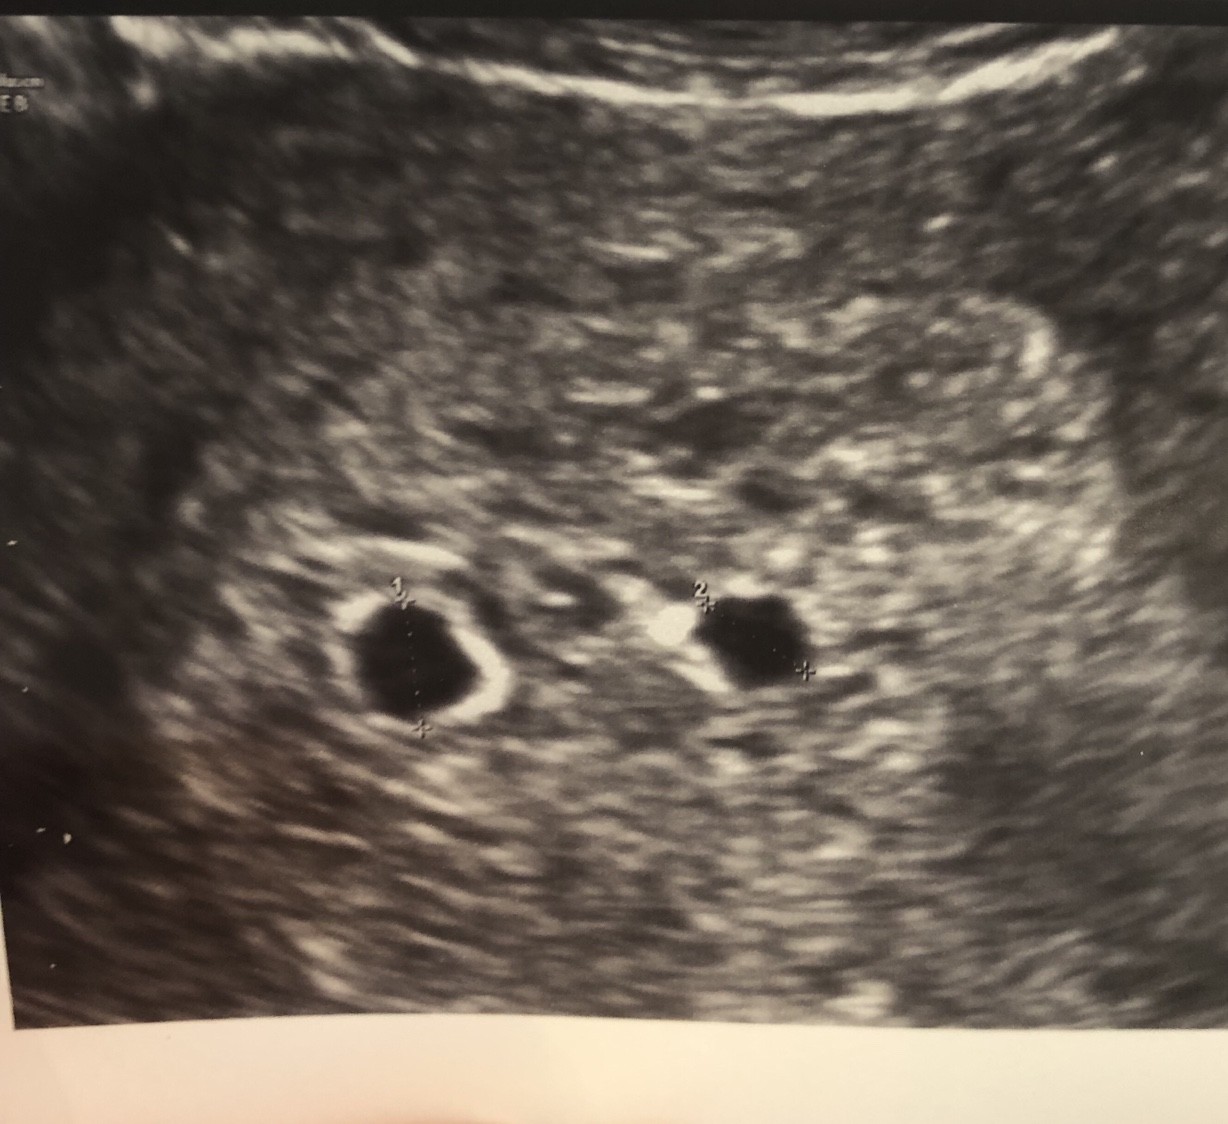

Poszłam na usg bo teraz jest jakoś inaczej ze robią położne prEd wizyta u lekarza i nagrywają to dla niego lub coś.

One mnie 10 razy pytały czy miałam podany jeden zarodek!

Wychodzi na to ze mam dwa pecherzyki!

Jestem w takim szoku ! Ja nawet nie wiedziałam ze jest możliwość ciąży bliźniaczej przy jednym!

Jestem w takim szoku ze prawie z fotela spadłam.[emoji79][emoji85]Zobacz załącznik 1058225